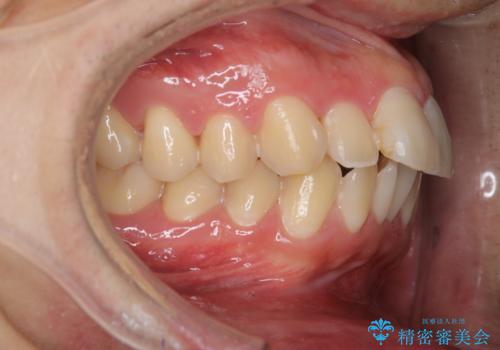

セラミックを付ける前にエアフローで綺麗ににクリーニング

- セラミックの詰め物を付ける前に、全体のクリーニングを希望とのことでした。

染め出しをし、歯磨き指導とクリーニング(エアフロー60分コース)を行いました。